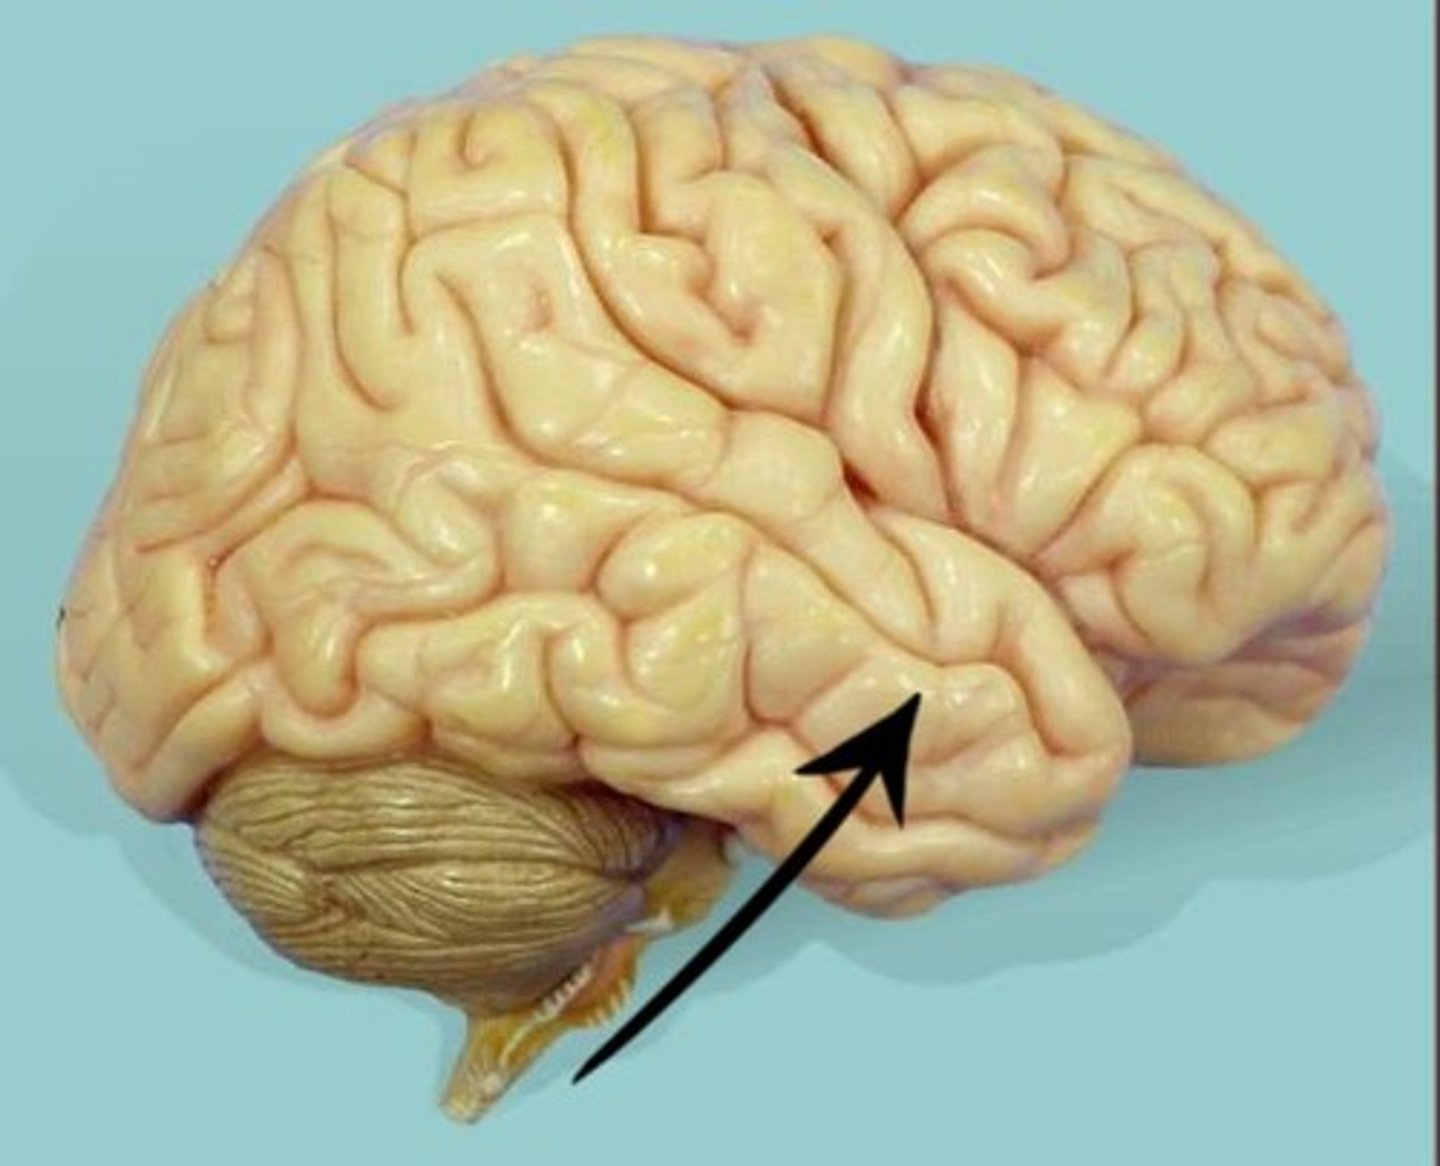

cerebellum

the "little brain" at the rear of the brainstem; functions include processing sensory input and coordinating movement output and balance

lateral fissure

The boundary between the frontal and temporal lobe.

tentorium cerebelli

the dura mater between the cerebellum and cerebrum.